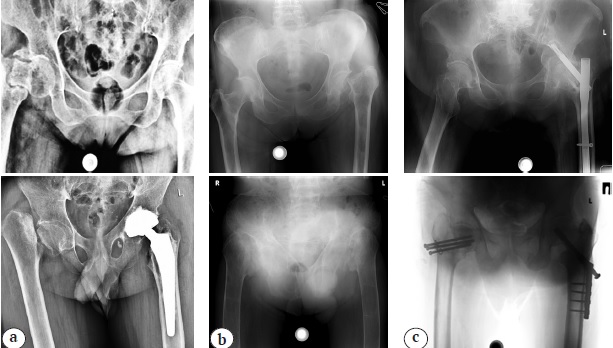

На сегодняшний день отсутствует общепринятая классификация ложных суставов ШБК, которая позволяла бы прогнозировать исход эндопротезирования тазобедренного сустава в зависимости от рентгенологических и функциональных изменений ПОБК. В связи с этим нами для проведения объективной оценки результатов проведенных операций предложено 3 классификационных типа псевдоартроза ШБК (рис. 1):

Рис. 1. Типы ложных суставов шейки бедренной кости по классификации авторов: а — тип А; b — тип В; c — тип С (объяснение в тексте)

Fig. 1. Types of the femoral neck false joints according to the authors’ classification: a — type A; b — type B; c — type C (explanation in the text)

Тип А — укорочение нижней конечности (не более 2 см); отсутствие дополнительных локальных признаков остеопороза (величина морфокортикального индекса Barnet – Nordin более 0,4 ед.); отсутствие функциональной недостаточности ягодичных мышц (способность пациента выполнять активные движения в тазобедренном суставе); отсутствие остеолизиса головки бедренной кости.

Тип В — укорочение нижней конечности более 2 см; признаки локального остеопороза (индекс Barnet-Nordin ≤0,4 ед.); функциональная недостаточность ягодичных мышц (отсутствие активных движений в тазобедренном суставе); остеолизис головки бедренной кости.

Тип С — псевдоартроз ШБК, осложненный наличием ранее установленного металлического фиксатора, который привел к инфицированию тазобедренного сустава и/или развитию дефекта вертлужной впадины или ПОБК в результате его миграции.